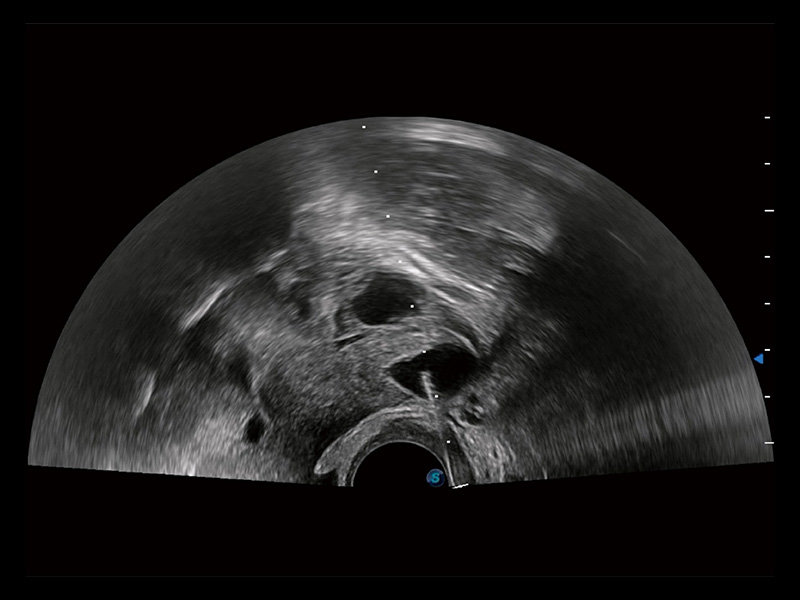

“生育问题”即关系民族复兴,也关系亿万家庭的幸福。随着婚育年龄推迟、社会压力增加等因素,越来越多人群也面临着“生不出、生不好”的问题。辅助生殖作为治疗不孕不育最有效的方法之一,也逐渐成为育儿新希望。而超声检查能为生殖需求人群的初诊评估提供宝贵的信息。 P20 Elite是开立医疗匠心打造的一款生殖应用型彩超。她继承开立医疗高端极光平台,突破性地将多款新型芯片及硬件模块进行整合,均衡了高端系统性能与小巧灵动机身。P20 Elite卓越的图像质量搭载专科探头,旨在为您提供全面的辅助生殖解决方案。

P20 Elite配备了丰富的生殖探头群和临床应用功能,在卵泡监测、穿刺取卵、胚胎移植、妊娠确认等领域,为生殖需求人群提供了新的临床机会,重新定义高端超声如何应用于生殖健康检查。